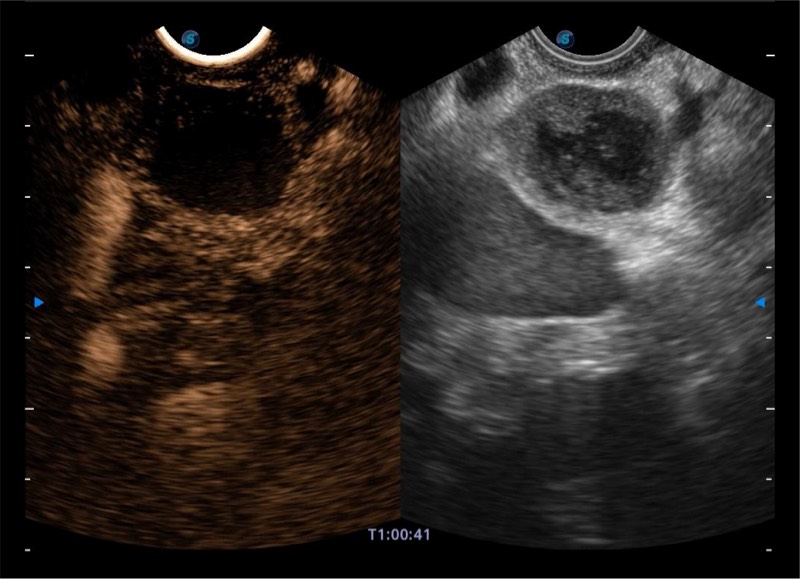

搭载百万级CMOS成像技术

及自主研发凸阵换能器,

可呈现优质的内镜和超声画面

基于二十年的超声技术积累,16877太阳集团提供了最新一代的独立超声主机,在提供高质量图像的同时满足多学科使用。具备常见多普勒技术并提供弹性成像、声学造影等高端影像技术。新一代传感器具有更强的抗干扰能力并减少图像伪影。

4-12MHZ宽频输出